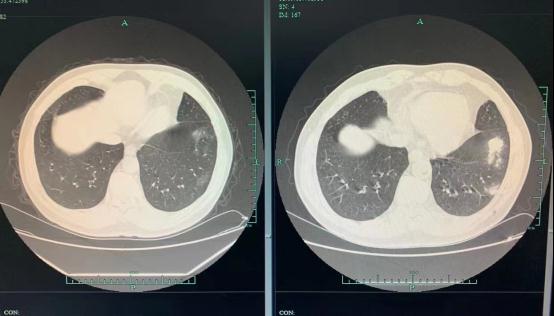

70岁的张大爷(化名)在一次体检中,肺部CT结果显示“多发肺结节”,几个团状阴影被医生指了出来。突如其来的结果把张大爷吓得不轻,赶紧来到杭州市第一人民医院呼吸与危重症医学科金华良副主任医师门诊。

3个月前、后

还好发现及时,只是轻度炎症,张大爷回家以后按照医嘱服用抗真菌药物,忍住不去西湖喂鸽子。经过3个月的治疗,张大爷再回到金医生门诊复查时,肺结节明显变小了,一家人这才松了口气。